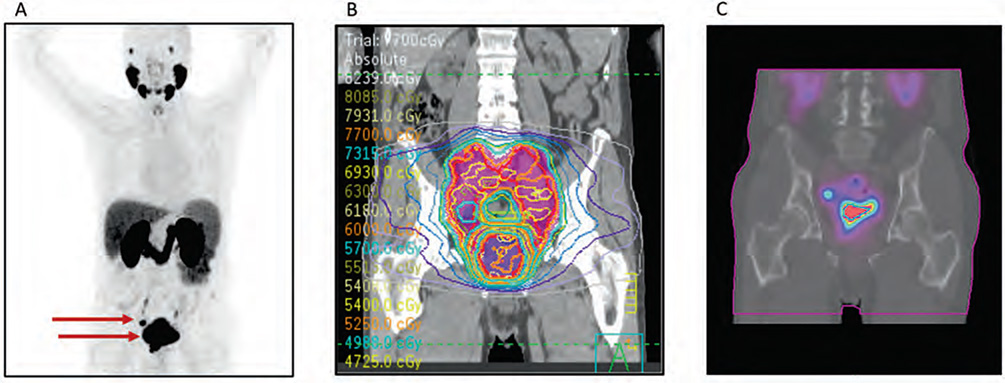

Figuur 12.1.

Voorbeeld van multimodale beeldvorming en behandelplanning. Ter illustratie tonen we beeld- en behandelingsgegevens van 1 patiënt: A) PSMA-PET/CT die radiotraceropname toont in de primaire prostaattumor en een locoregionale lymfeklier (aangegeven met rode pijlen); B) EBRT-planning die de dosisverdeling in het bestralingsveld weergeeft, waarbij een totale dosis van 78 Gy aan de prostaat wordt toegediend; en C) post-behandelingsdosimetrie SPECT/CT na toediening van [177Lu] Lu-PSMA-617, met een geschatte geabsorbeerde dosis van 38,7 Gy aan de prostaat en 24,0 Gy aan de lymfeklier

Prostaatkankerpatiënten met locoregionale lymfeklieren (N1M0) hebben een beperkte prognose ondanks agressieve multimodale behandeling met uitwendige bestralingstherapie (EBRT) en androgeendeprivatietherapie (ADT). [177Lu]Lu-PSMA-617 heeft reeds veelbelovende resultaten laten zien in een palliatieve setting bij prostaatkanker. Deze studie onderzoekt de veiligheid van EBRT en ADT in combinatie met [177Lu]Lu-PSMA-617 voor N1M0-patiënten met prostaatkanker, in een curatieve setting.

De PROQURE-I-studie is een multicenter fase I-studie die de standaardbehandeling (6–7 weken EBRT en 2 jaar ADT) onderzoekt met 1–2 toegevoegde cycli (3, 6, 9 of 2 × 7,4 GBq) [177Lu] Lu-PSMA-617 gegeven tijdens week 2 (en 4) van de EBRT. De maximaal tolereerbare hoeveelheid radioactiviteit wordt bepaald met een Bayesian Optimal Interval (BOIN)-dosisescalatie, met als criterium het optreden van graad 3 of hogere toxiciteit, gemeten tot 3 maanden na de behandeling. De gecombineerde geabsorbeerde dosis van EBRT en [177Lu]Lu-PSMA-617 is een van de secundaire uitkomsten.

12.3 Resultaten

In totaal werden 14 patiënten geïncludeerd. Eén patiënt ontving 3 GBq, 1 patiënt 6 GBq, 6 patiënten 9 GBq en de laatste 6 patiënten 2 × 7,4 GBq [177Lu]Lu-PSMA-617. Alle patiënten vertoonden graad 1–2 toxiciteit, die was toe te schrijven aan de EBRT. Er werd geen graad 3 toxiciteit waargenomen. Het hoogste en goed verdragen dosisniveau van [177Lu]Lu-PSMA-617 gaf een extra geschatte geabsorbeerde dosis in de primaire tumor van gemiddeld 10,2 Gy (range 5,1–15,4), bovenop de maximale 78 Gy van EBRT.

12.4 Conclusie